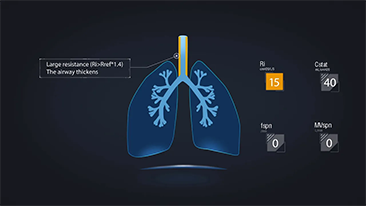

Dengan wawasan mendalam tentang kebutuhan klinis pasien dan perawat, ventilator Mindray mendukung kebutuhan terapi berurutan antara terapi oksigen, ventilasi non-invasif, dan ventilasi invasif dengan kinerja stabil, fungsi serbaguna, dan kemudahan penggunaan. Mode ventilasi dan alat pendukung pengambilan keputusan dikembangkan berdasarkan kebutuhan klinis dan pedoman profesional, untuk membantu petugas medis mengambil keputusan klinis dengan tenang pada semua populasi dan tingkat ketajaman pasien.

Memilih pengaturan ventilator yang tepat untuk pengobatan pasien dengan penyakit saluran pernapasan merupakan masalah yang cukup penting. Karena tugas menentukan parameter peralatan ventilasi sepenuhnya dilakukan oleh dokter, pengetahuan dan pengalaman dokter dalam pemilihan pengaturan ini memiliki efek langsung pada keakuratan keputusannya. Paradigma perawatan suportif pasien telah berubah secara signifikan selama 20 tahun terakhir. Saat ini, berbagai mode ventilasi dan alat pendukung keputusan telah dikembangkan seputar kebutuhan klinis untuk membantu membantu pengasuh meningkatkan efisiensi dan menghilangkan kesalahan dalam keputusan klinis.

Mengintegrasikan terapi oksigen aliran tinggi, ventilasi non-invasif, dan ventilasi invasif, ventilator Seri SV 3-in-1 menyatukan kinerja yang stabil, fungsi serbaguna, dan kemudahan penggunaan. Fitur pelindung paru-paru yang luar biasa dan banyak alat pendukung keputusan dirancang untuk mengurangi risiko infeksi silang dan memudahkan rutinitas harian pengasuh.